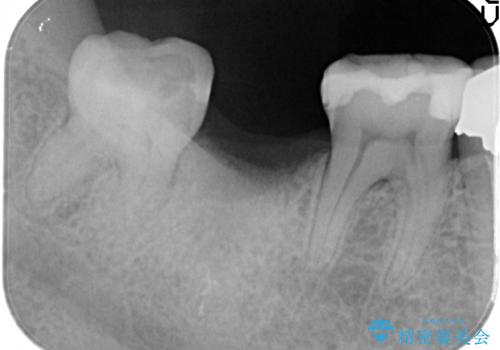

- 右下の奥歯をかぶせ物がとれたまま放置しているところに歯を入れたいとのことで来院されました。

精査すると保存が難しいため抜歯をして、インプラントを埋入、かぶせ物を装着する計画としました。